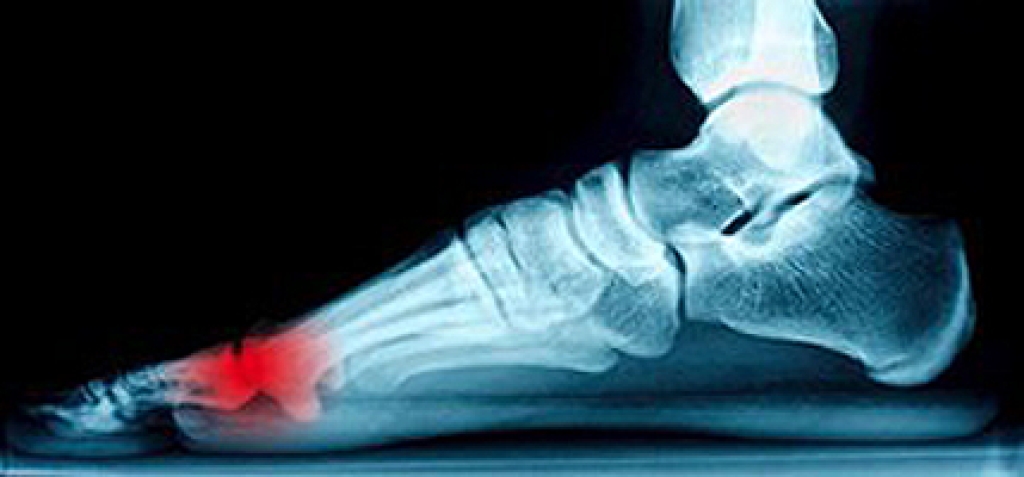

There are two bones that are located under the bottom of the big toe that are referred to as the sesamoid bones. If they should become inflamed, which may be the result of injury or overuse, sesamoiditis may develop. Many patients will experience pain if that area of the foot is touched, and may have difficulty in walking. A proper diagnosis is necessary to perform before beginning the correct treatment, which typically includes having an X-ray taken, or obtaining a bone scan or MRI. Mild relief may be found when there is additional cushioning added to the shoes, which may be effective in relieving a portion of the pressure. It may be beneficial to refrain from the activities that may have caused this condition, and comfort may be found when the foot is resting. If you have pain under the big toe, it is advised to schedule a consultation with a podiatrist who can properly treat sesamoiditis.